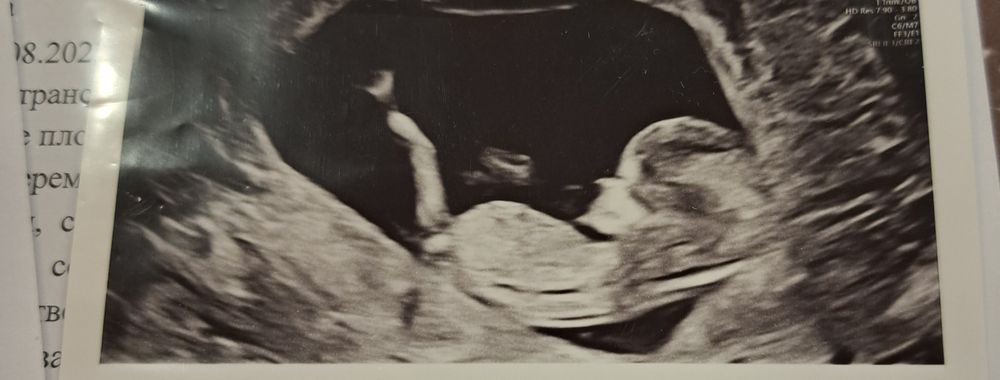

12 недель🤰

Токсичные свекр и свекровь УЗИ 12 недель